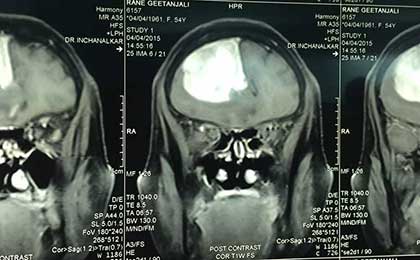

frontal epidermoid pre t2w

• frontal epidermoid pre t2w